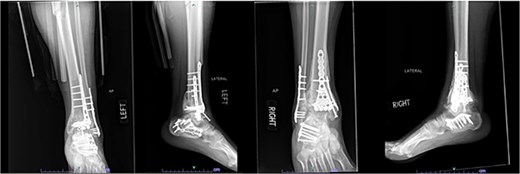

A 57-year-old male with a body mass index (BMI) of 48.7 kg/m2 and multiple comorbidities, including asthma, coronary artery disease, hypertension, hyperlipidemia, ischemic cardiomyopathy, obstructive sleep apnea, and hypothyroidism, following a motor vehicle collision when he lost control of his vehicle due to a coughing spell. His injuries included bilateral pilon fractures (Fig. 1), a T2 superior endplate fracture, and bilateral pulmonary contusions. He initially presented to a regional hospital and was transferred to our facility 10 days after the injury.

Anterior-to-posterior (AP) radiographs of patient 1 obtained 10 days after injury, upon transfer to our facility, demonstrating bilateral pilon fractures.